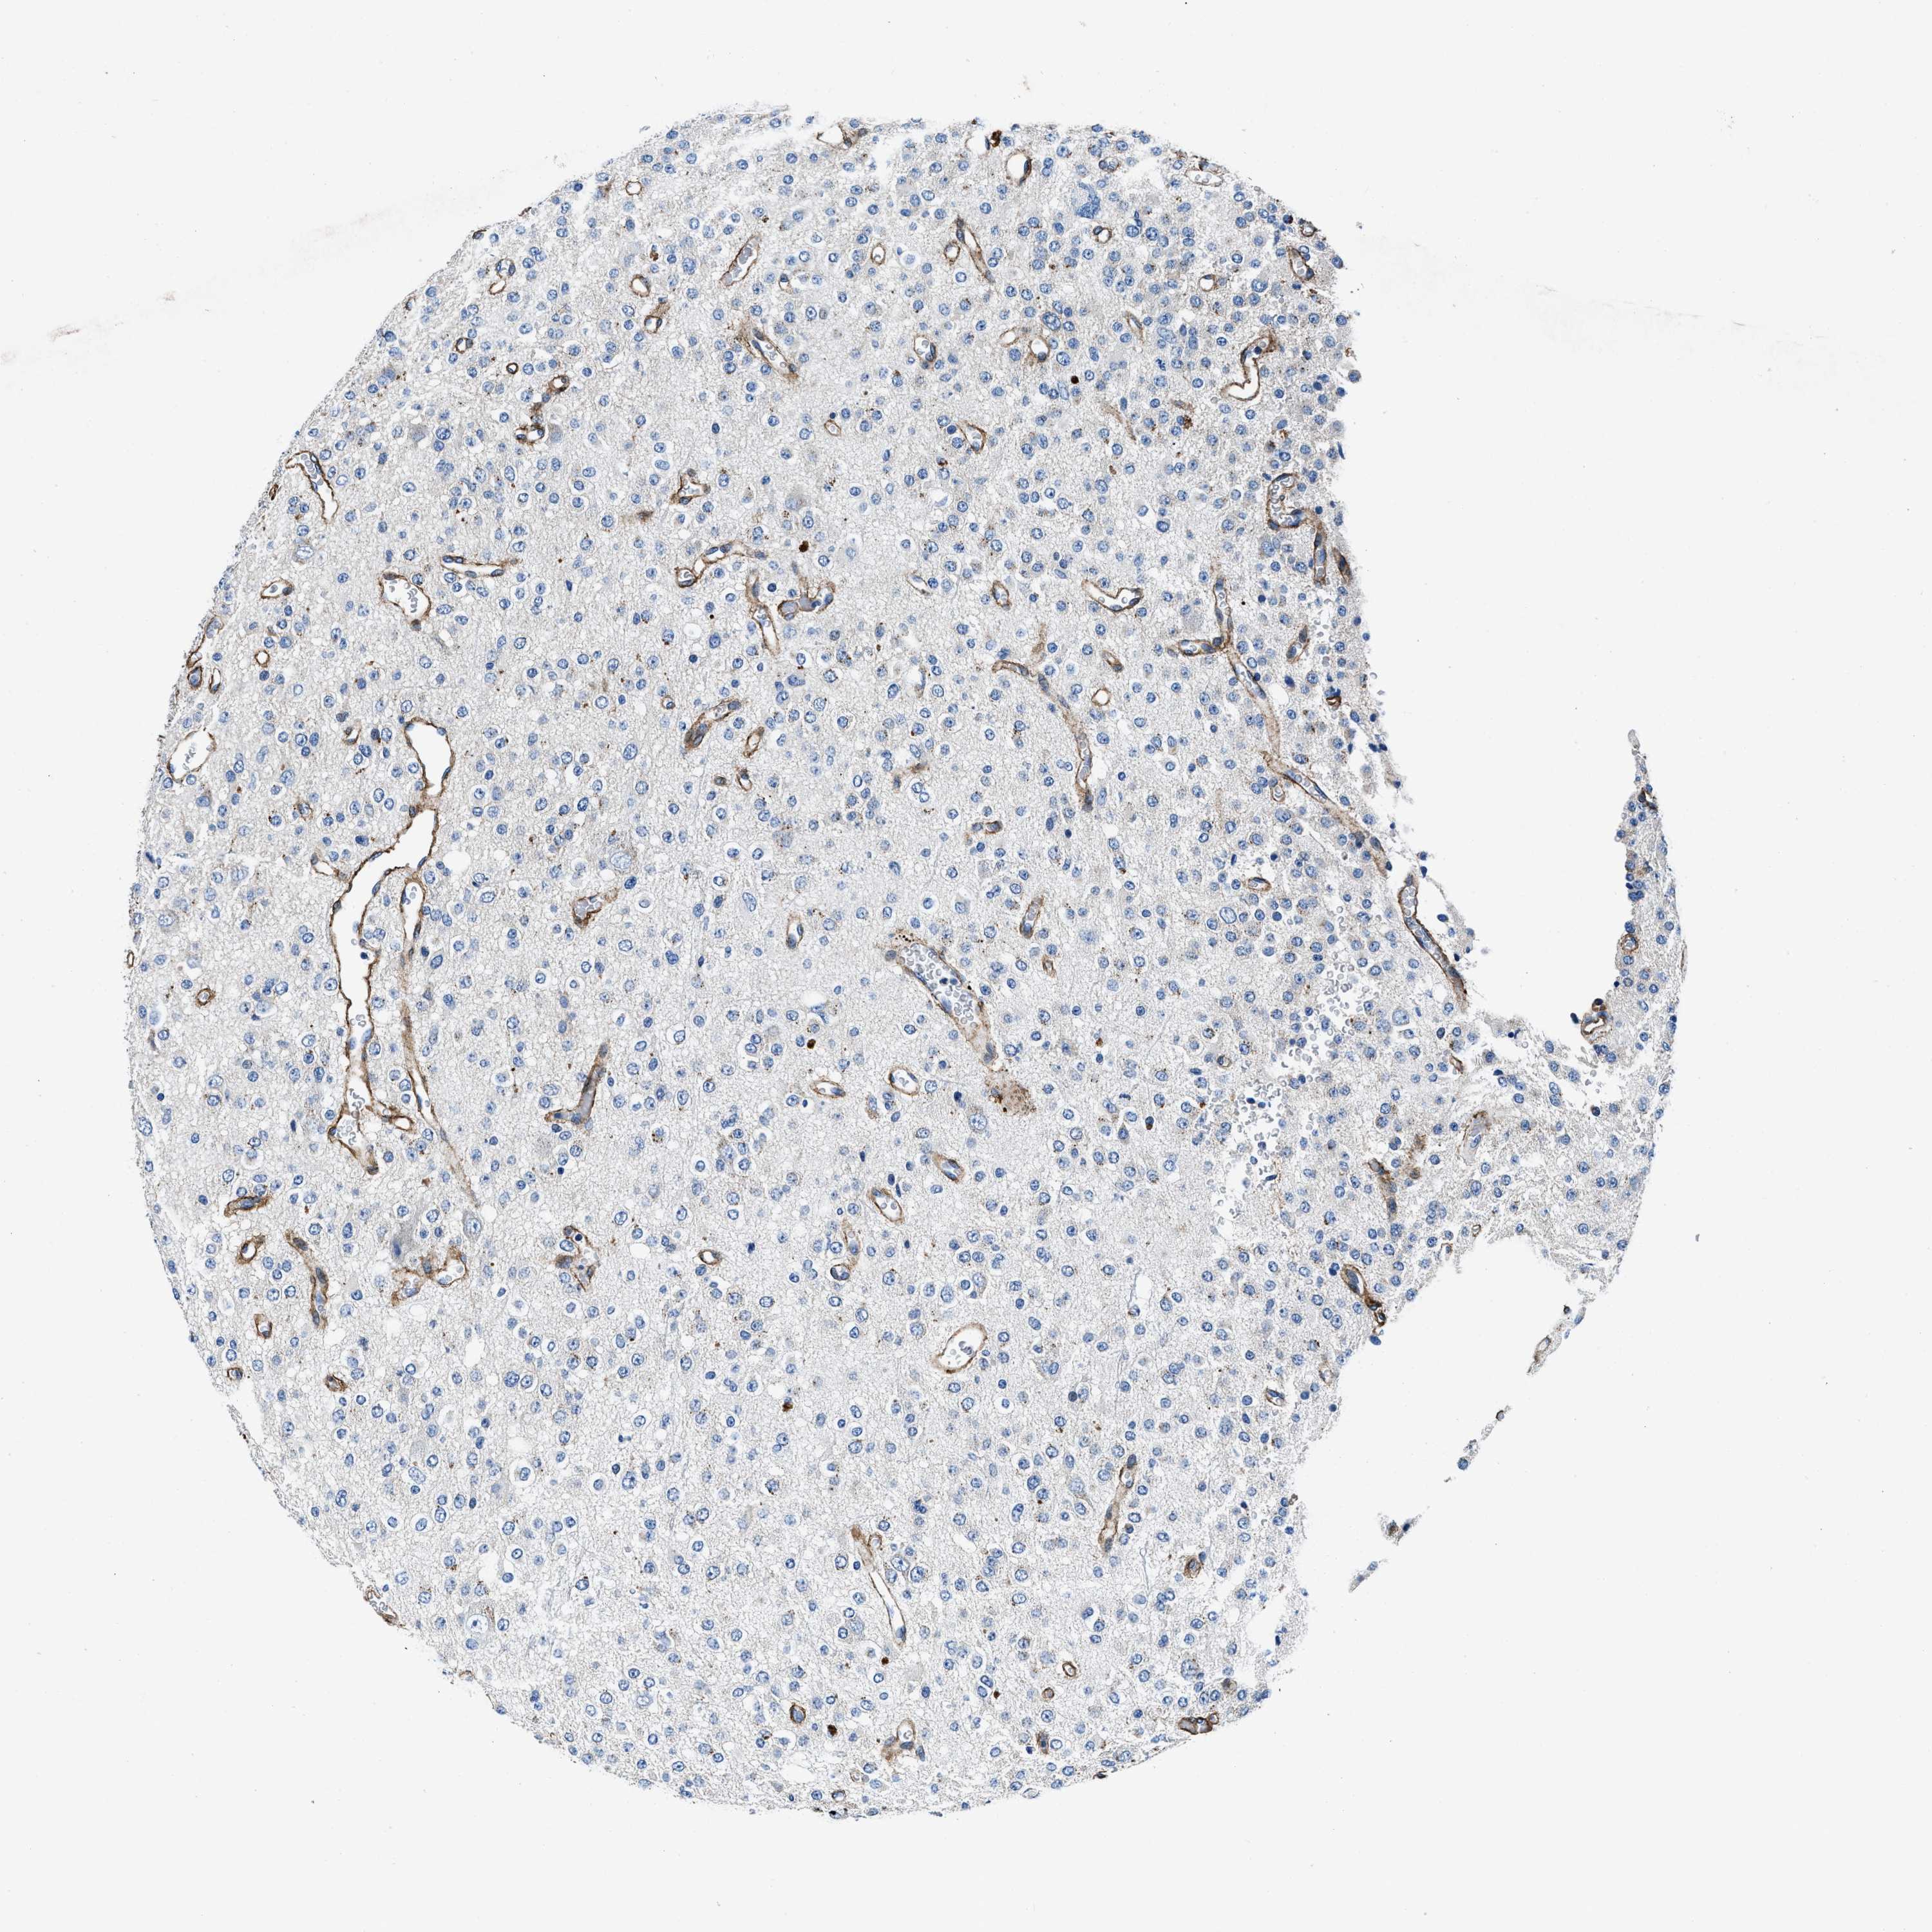

GLIOMA - Protein expressioni

A mouse-over function shows sample information and annotation data. Click on an image to view it in a full screen mode. Samples can be filtered based on level of antibody staining by selecting one or several of the following categories: high, medium, low and not detected. The assay and annotation is described here.

Note that samples used for immunohistochemistry by the Human Protein Atlas do not correspond to samples in the TCGA dataset.

Antibody stainingi

Antibody staining in the annotated cell types in the current human tissue is reported as not detected, low, medium, or high, based on conventional immunohistochemistry profiling in selected tissues. This score is based on the combination of the staining intensity and fraction of stained cells.

Each image is clickable and will lead to virtual microscopy that enables deeper exploration of all samples and also displays staining intensity scores, fraction scores and subcellular localization as well as patient and tissue information for each sample.

Antibody CAB001960

Antibody CAB016353

Staining

High

Medium

Low

Not detected

Intensity

Strong

Moderate

Weak

Negative

Quantity

>75%

75%-25%

<25%

None

Location

Nuclear

Cytoplasmic/membranous

Cytoplasmic/membranous,nuclear

Glioma, malignant, High grade

Glioma, malignant, Low grade